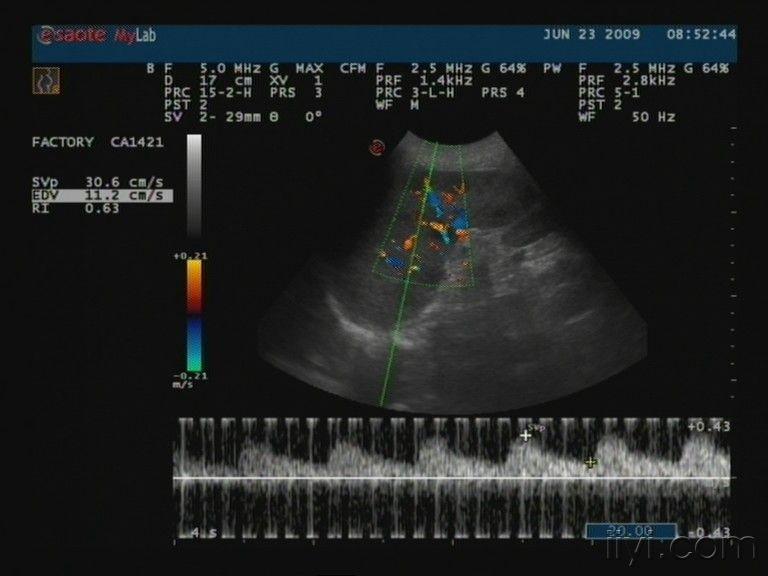

脾脏疾病影像诊断.

脾脏肿瘤